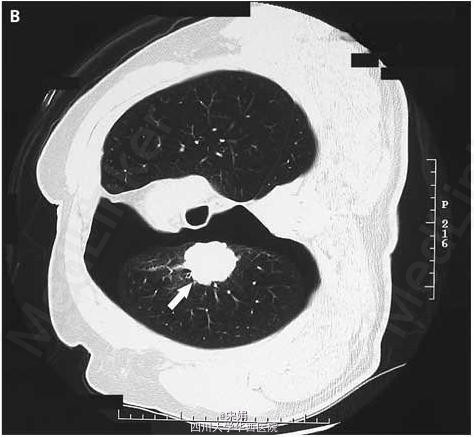

对肿块进行穿刺活检,结果导致右侧气胸,进而复查CT图像发现,当病人右侧卧位时,肿块随肺而动,与气管和纵膈完全分开。行右肺上叶切除术,术后病理结果为腺癌,未侵及脏层胸膜。

患者恢复良好,1年随访无复发征象。这个病例非常巧合,穿刺造成气胸,反而提供了有用的肿瘤分期信息。 DOI: 10.1056/NEJMicm061662